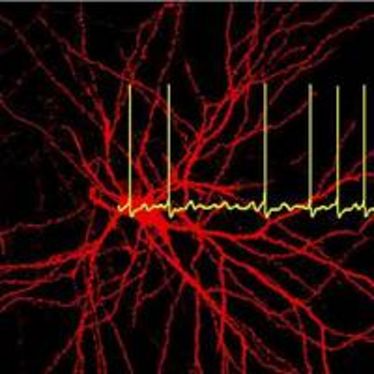

Neurologisches Seminar: K2P Kanäle - von den physiologischen Grundlagen zur Pathophysiologie

Neurologisches Seminar: K2P Kanäle - von den physiologischen Grundlagen zur Pathophysiologie

Neuroscience Colloquium

Neuroscience Colloquium

Neuroscience Colloquium

Neuroscience Colloquium

Cells in Motion BrownBagLunch: Role of the Ubiquitin System in Developmental Neurodegeneration

Cells in Motion BrownBagLunch: Role of the Ubiquitin System in Developmental Neurodegeneration

Neurovascular Day 2013

Neurovascular Day 2013